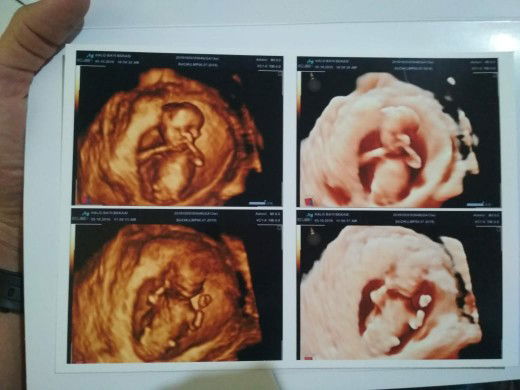

happy wife, happy momy soon